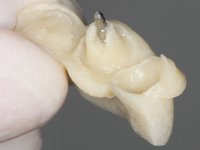

Endodontic treatments were performed and a metalic non screwed intra radicular post was placed on tooth 1.1. An alginate impression was made for laboratory confection of a reinforced acrylic provisional bridge, with teeth 1.1 and 2.2 as abutments and 2.2 as a pontic. After preparation of tooth 1.1 and root preparation of 2.1, the bridge was relined in mouth with self-polymerizable acrylic using a metal post for further retaining the prepared root canal on 2.1. Tooth 2.2 was cut at the gingival level to function as support. In the same session, the impression of the root canal of the 2.1 was made for the laboratory confection of a cast post and core. A double mixture technique with plastic tutor was used after previous canal vaseline with endodontic file and cotton. The provisional bridge was provisionally cemented and the cast post and core was made in the laboratory. Cast post and core cementation was made with resin-reinforced glass ionomer cement and the provisional bridge had to be readjusted to the new situation by removing the post at the site of 2.1. After careful surgical planning, a dental implant was placed, simultaneously with extraction of the root of tooth 2.2. The provisional bridge was placed by resting on the healing screw placed in the implant. The respected osteointegration period was 12 weeks, during which the provisional bridge was relined twice. After complete maturation of hard and soft tissues, definitive impressions were made. The gingival retraction technique was applied with an impregnated retraction cord and impression was performed using double mixture, open tray impression technique. A custom precious metal abutment implant was prepared in the lab, along with 3 metal caps to be used as infrastructures for the metal ceramic crowns. Particular care was taken in the confection of the cervical finishing line of the implant abutment, in order to follow the soft tissues emergence profile. Proof of infrastructures was done in the mouth being evaluated clinically and imagiologically. Collection of color information was done by the ceramist at the office. Ceramic was applied in the laboratory and the finished work was placed in the mouth after approval by the patient. Definitive cementation was made with resin-reinforced glass ionomer cement, and the first crown to be cemented was that of the implant, to facilitate removal of the excess.